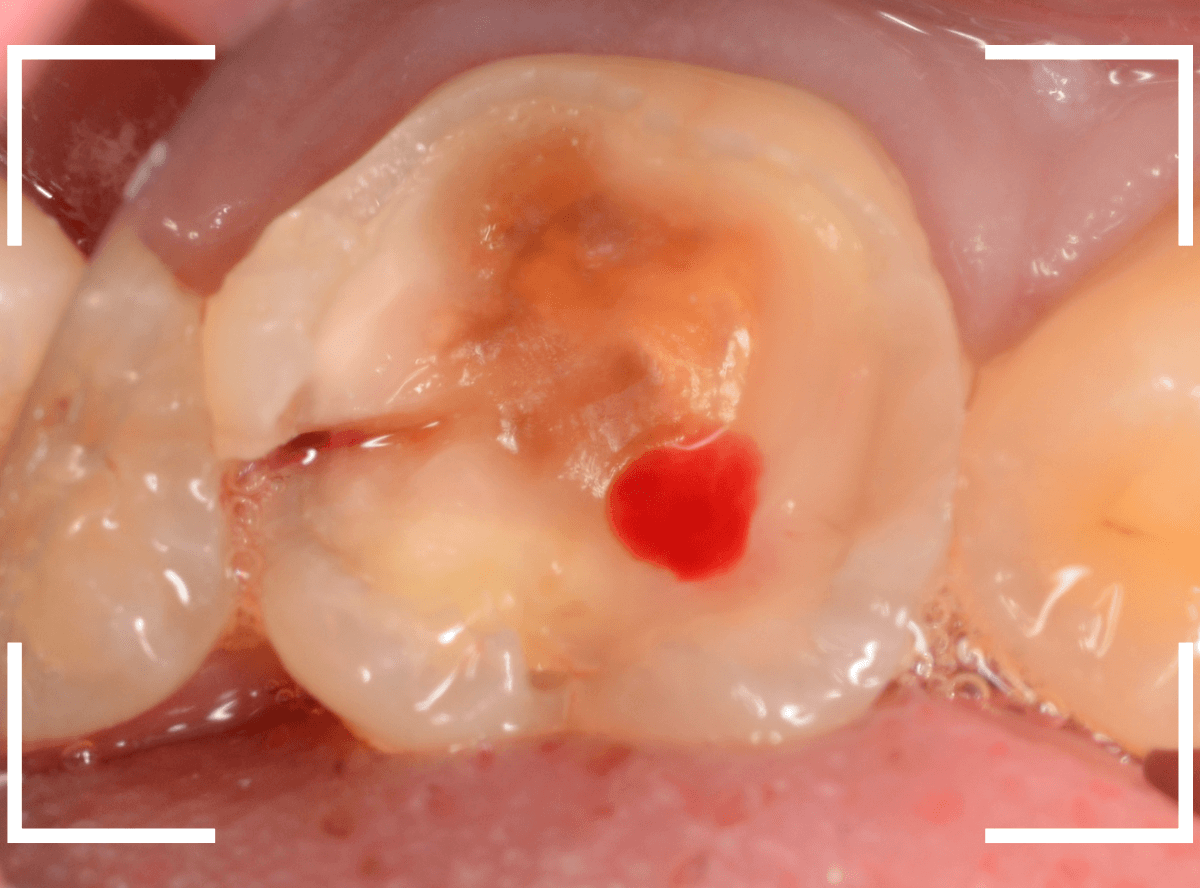

Case.20 劣化したレジン側面から進行した虫歯

「つめものが欠けたまま長期間放置して、歯がしみる」という訴えで来院された患者さんさんです。

拝見すると、劣化したレジンが欠けて、中で虫歯になっているのがわかります。

・欠けたまま長期間放置した

・しみるという自覚症状がある

事から、中で深い虫歯になっている事が想像されます。

レントゲン写真で確認します。

赤い線がレジンが入っている部分。

青い線が歯の神経です。

かなり神経の近いところまでレジンがつめてあるのがわかりますが、虫歯が側面からどの程度進んでいるのかはよくわかりません。

レントゲン写真だけみると、治療の必要がなさそうにも見えます。

このように、初見では虫歯になっている事が明らかなのに、レントゲン写真ではまったくわからないとう事もあります。

レジンを外しながら、虫歯を確認します。

慎重にレジンを除去しましたが、途中で露髄(神経が露出する事)しました。

歯の神経の中には、血管も含まれているので、神経が露出すると、このように出血します。

「しみる、痛い」などの明確な強い症状がある場合、このような状況の事が多いです。

今回は出血量が多く、神経を除去する治療(抜髄)の可能性が高いとも感じましたが、できる限り神経を保存する方法を取ることにしました。

神経を保護するお薬をつめて蓋をしてしばらく経過観察します。

神経を除去すると、治療期間が長引くうえに、歯の寿命がとても短くなってしまいます。

できるだけ歯の神経を残すためには、症状が出てからの歯科受診ではなく、定期的なメンテンナンス受診を続けるようにしてください。